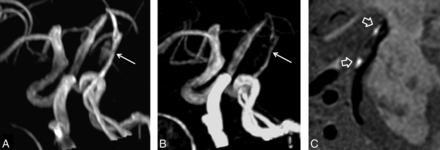

In measuring luminal stenosis of diseased arteries, the Cohen κ value between 3D TOF MRA and SNAP imaging was 0.82 (P < .001). Figure 1 demonstrates mild stenosis in the basilar artery on the MRA image derived from SNAP imaging (Fig 1A), corresponding to the TOF MRA image (Fig 1B), while the hyperintense signal on the SNAP vessel wall image (Fig 1C) indicates IMH. One patient with mild stenosis on 3D TOF MRA was classified as having moderate stenosis by SNAP imaging, and 2 patients with severe stenosis on 3D TOF MRA were diagnosed as having occlusion. All IMHs on multisequence imaging were successfully identified by SNAP imaging. IMH appeared hyperintense on the 3D SNAP image, corresponding to the 3D MERGE images (Fig 2). In addition, the characteristics of pseudoaneurysm, intimal flaps, and double lumen on multisequence imaging were also accurately determined by SNAP imaging (Fig 3). Figure 4 is an example of the excellent joint visualization of luminal changes and IMH in the vessel wall on SNAP images after color-coded reconstruction.

Excellent agreement between SNAP imaging and TOF MRA in measuring stenosis. Mild stenosis in the basilar artery is determined by MRA images derived from SNAP imaging (A), which corresponds to the TOF MRA image (B). The hyperintense signal on the SNAP vessel wall image (C) indicates intramural hematoma.

SNAP imaging delineates the intimal flaps. The SNAP MRA image (A) shows a dilated lumen (pseudoaneurysm) in the internal carotid artery. The intimal flaps (hollow arrow) and double lumen (white arrow) are noted on vessel wall images derived from SNAP imaging in the coronal (B) and axial (C) views after MPR reconstruction. The white line on the coronal view indicates the location of the axial view acquisition.